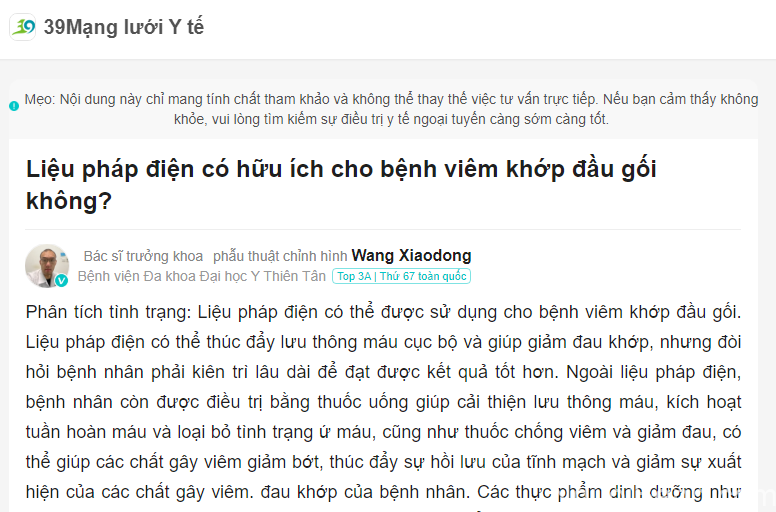

5.7. Chia sẻ từ Bác sĩ Liu Yongxiang và Bác sĩ Wang Xiaodong – Sử dụng liệu pháp điện cho bệnh viêm khớp gối

Các bác sĩ có uy tín đến từ những bệnh viện lớn đã giải đáp thắc mắc về đều trị bệnh viêm khớp gối bằng phươn pháp điện trị liệu:

Bác sĩ Liu Yongxiang – Phó trưởng khoa Phẫu thuật chỉnh hình, Bệnh viện Yên Đài:

Chia sẻ từ bác sĩ Liu Yongxiang (GG dịch tự động)

Bác sĩ Wang Xiaodong – Trưởng khoa Phẫu thuật chỉnh hình, Bệnh viện Đa khoa Đại học Y Thiên Tân:

Chia sẻ từ bác sĩ Wang Xiaodong (GG dịch tự động)